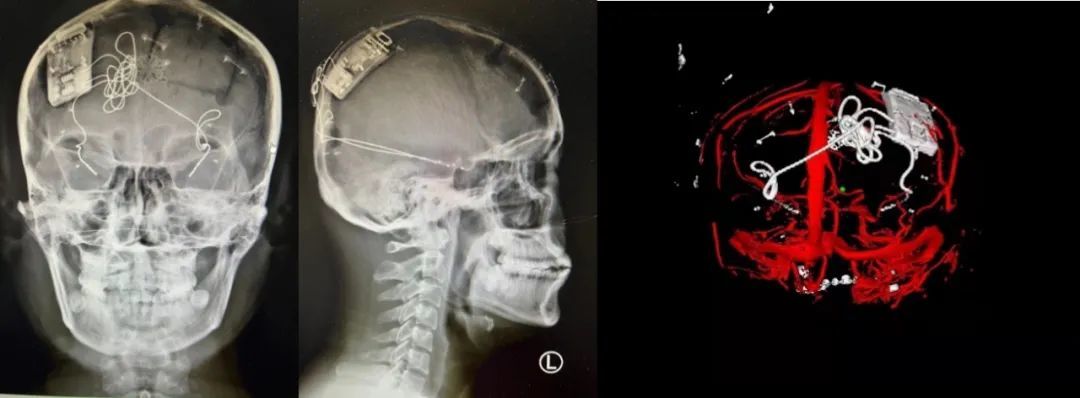

本次手術(shù)過程順利,術(shù)中刺激器各項指標均工作正常,術(shù)后重建顯示電極位置精準,腦電信號清晰。患者為男性,入院后診斷為雙側(cè)顳葉癲癇,此類癲癇為開顱手術(shù)的相對禁忌癥,在藥物無法控制的情況下,傳統(tǒng)治療效果欠佳 。

術(shù)前經(jīng)過宣武醫(yī)院癲癇多學科專家團隊詳細的臨床評估,包括視頻腦電監(jiān)測、頭顱磁共振及三維 CT 掃描、腦核醫(yī)學檢查等,全面評估了患者病情及致癇灶定位情況。

由于患者臨床診斷為雙側(cè)顳葉癲癇伴海馬硬化,無法通過致癇灶切除等傳統(tǒng)外科手術(shù)方式獲益,決定進行閉環(huán)反應(yīng)性神經(jīng)刺激系統(tǒng)植入手術(shù)治療。并根據(jù)閉環(huán)神經(jīng)刺激技術(shù)特點,為患者“量身定制”植入方案,尤其是電極植入位點和脈沖發(fā)生器固定部位等,為手術(shù)的順利實施奠定了良好基礎(chǔ)。

團隊根據(jù)術(shù)前計劃,在手術(shù)機器人輔助下完成雙海馬長軸電極及 IPG 植入,術(shù)后重建顯示電極位置精準,腦電信號清晰。術(shù)后第二天,患者即下床活動,身體狀況恢復(fù)良好。